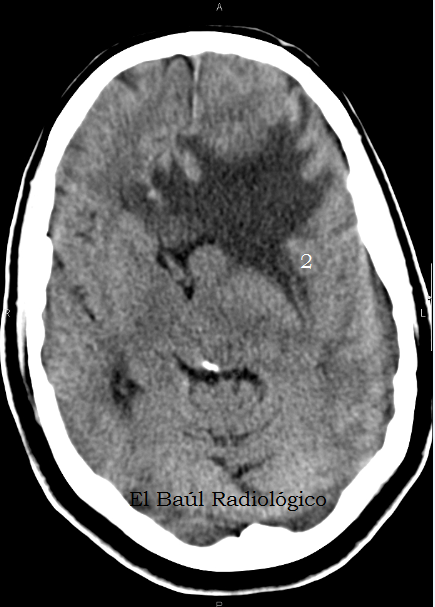

FIGURA 3) Más edema vasogénico digitiforme. ¿.....?

(More digitiform vasogenic edema. .....?)

FIGURA 4) Y más edema que desplaza las estructuras de la línea media en sentido contralateral. ¿....?

(And more edema which displaces the midline structures in the contralateral sense. ....?)